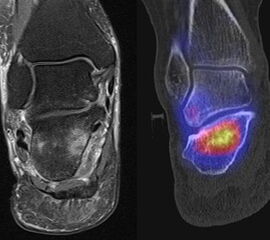

Abbildung 8.1. a bis f.: Patient mit Z. n. OSG-Distorsion vor 8 Monaten und konservativer Therapie. Anhaltende Schmerzen im Bereich des linken Innenknöchels. Im MRT bestand der Verdacht auf eine symptomatische kleine osteochondrale Läsion im medialen linken Talus (Abbildung 8.1. a und c). Zur weiteren Klärung erfolgte eine SPECT/CT 30 Tage später, welche jedoch im Gegensatz zur MRT eine fokale Mehrspeicherung an der tibialen Insertion des Deltabandes nachwies. Die Tatsache, dass die SPECT/CT spezifischer als die MRT symptomatische Bandläsionen detektieren kann wird untenstehend ausführlich thematisiert.